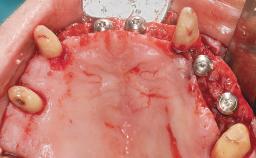

Conventional Loading of Eight Implants in the Maxilla and Final Restoration with a Full-Arch Gold-Ceramic FDP

A 35-year-old Caucasian female presenting with advanced periodontal disease involving both the maxillary and the mandibular dentition was referred for evaluation. The patient, a non-smoker in good general health, requested treatment for recurrent periodontal abscesses, tooth mobility, and discomfort during chewing, as well as restoration of her missing teeth with a fixed prosthesis to improve mastication and esthetics. All residual maxillary teeth exhibited plaque deposits, deep pockets, bleeding on probing, and class III mobility and were evaluated as hopeless. All residual mandibular teeth except tooth 37 could be maintained after periodontal therapy.

# of Implants 8

Bone Augmentation Horizontal|Staged|Vertical

Augmentation Materials Autogenous block(s)

Soft Tissue Grafting Staged